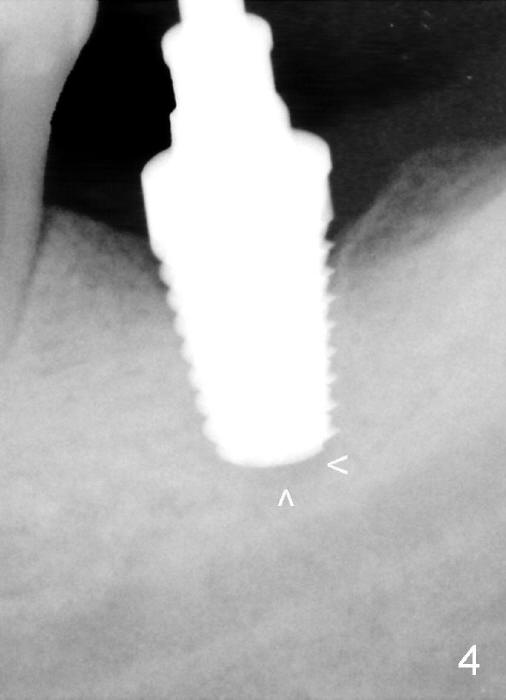

In the 2nd procedure, osteotomy is deepened by approximately 2 mm. A 7x14 mm tap is inserted (Fig.4). There is apical space (arrowheads) to be engaged further.